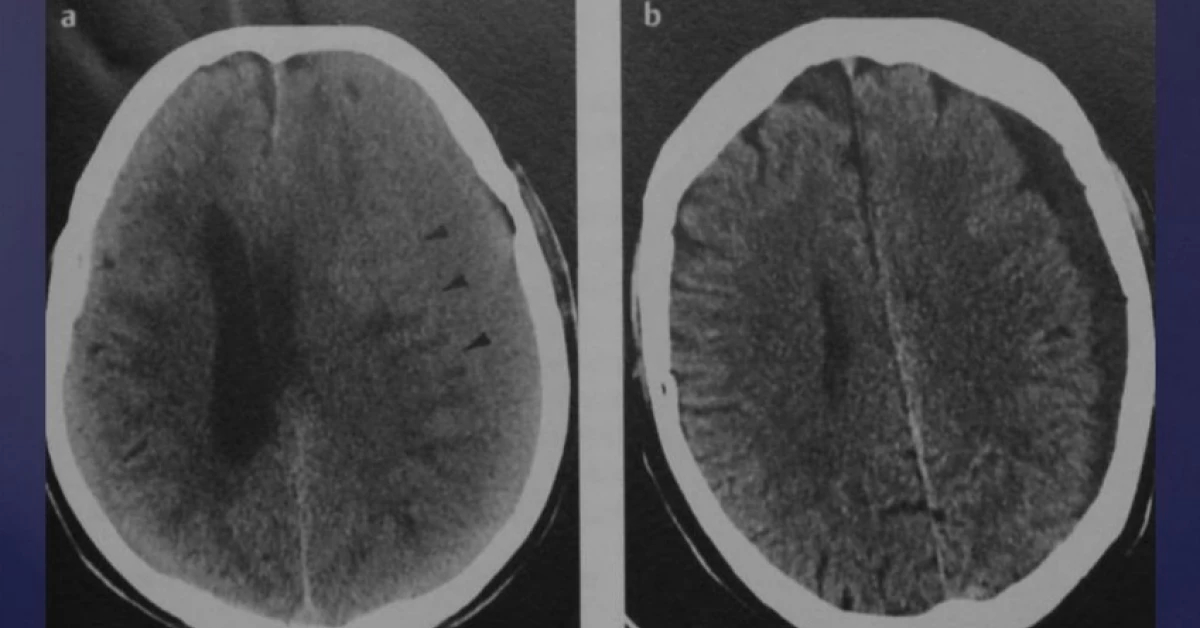

Субдуральная гематома диагностика